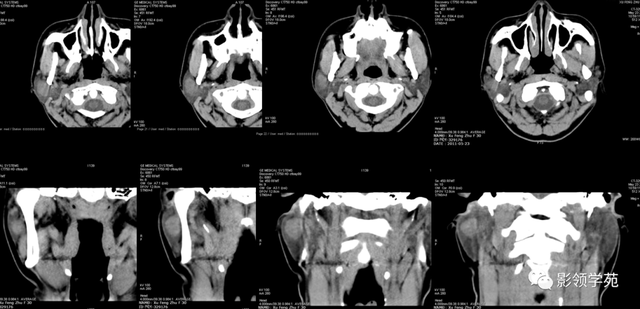

图6 a 、b 、c 囊腺癌 左侧腮腺弥漫性增大,密度增高,边缘无法确定,同侧颈部可见淋投合肿大坏死,胸锁乳突肌受侵占

【影像体现】:右侧腮腺不规则增大,边缘强化不规则,CT值为15-44HU,内有低密度坏死区,且见脱离 ,周围显着 强化,未见肿大淋投合。

【影像诊断】:右腮腺脓肿。

2.腮腺脓肿:体现为腮腺局限性肿块并黑点状坏死,典型者可见环状强化,伴相近 筋膜增厚和皮下脂肪层模糊,团结 临床局部皮温升高可诊断。